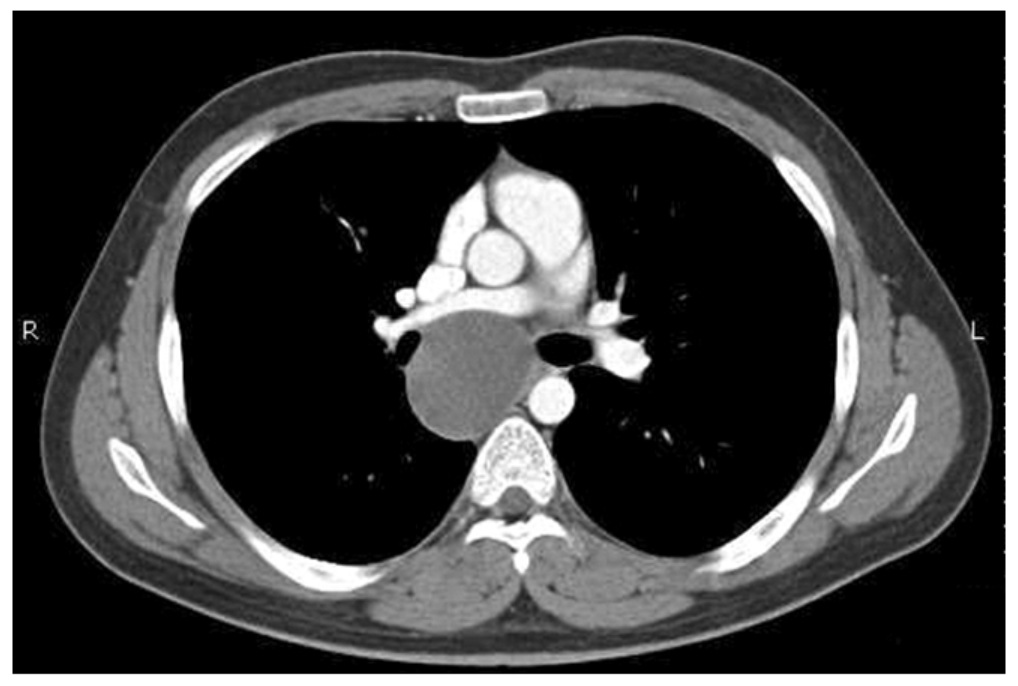

20¼¼ ³²ÀÚ, ½Åü °ËÁø X-ray »ó ¿ì¿¬È÷ ¹ß°ßµÈ ÀÌ»ó ¼Ò°ß ÁÖ¼Ò·Î ³»¿øÇÏ¿´½À´Ï´Ù.

Ưº°È÷ È£¼ÒÇÏ´Â Áõ»óÀº ¾ø¾ú°í lab »ó ÀÌ»ó ¼Ò°ßÀº º¸ÀÌÁö ¾Ê¾Ò½À´Ï´Ù.